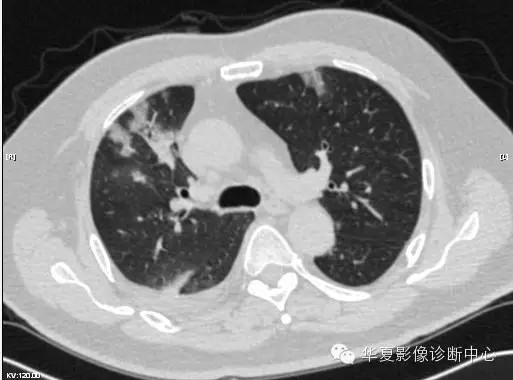

【病例学习】甲型H7N9禽流感一例

男性 63

发热咳嗽5天

2013-4-5拍片示右肺实变,收入院,追问病史,发病期间肌肉酸痛,头痛,无腹痛腹泻,无明显胸闷气急,无意识改变。有高血压病史,无其它病史。

2013-4-7CT进一步检查。

最终诊断:H7N9。